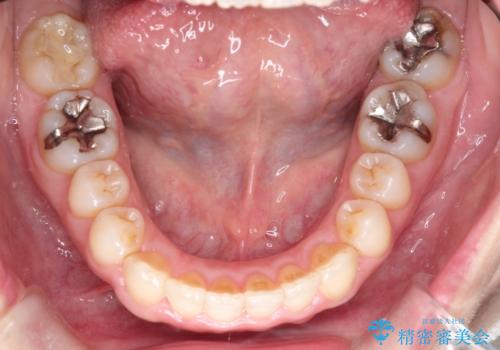

【インビザライン 】前歯のガタガタを治したい

- 前歯のガタガタを主訴に来院されました。

インビザライン で治療しました。途中は使用時間が20時間を切ることもありましたが、それでも頑張って使っていただき1年半で矯正終了することができました。